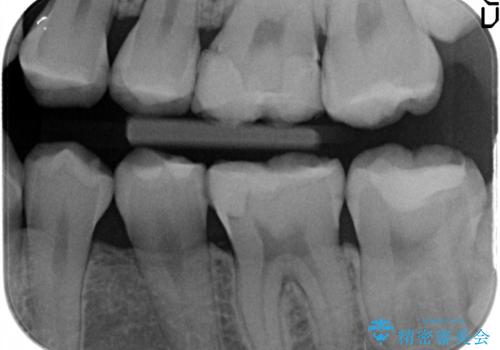

- 奥歯のプラスチックが劣化して二次的に虫歯ができているのを治療しました。

プラスチックがすり減り歯の高さが少ないため、薄くても丈夫なセラミックのかぶせ物(クラウン)を選びました。

大臼歯にプラスチックで広範囲に治療することは劣化も激しくなり長期的な予後を考えると全くお勧めしない治療です。